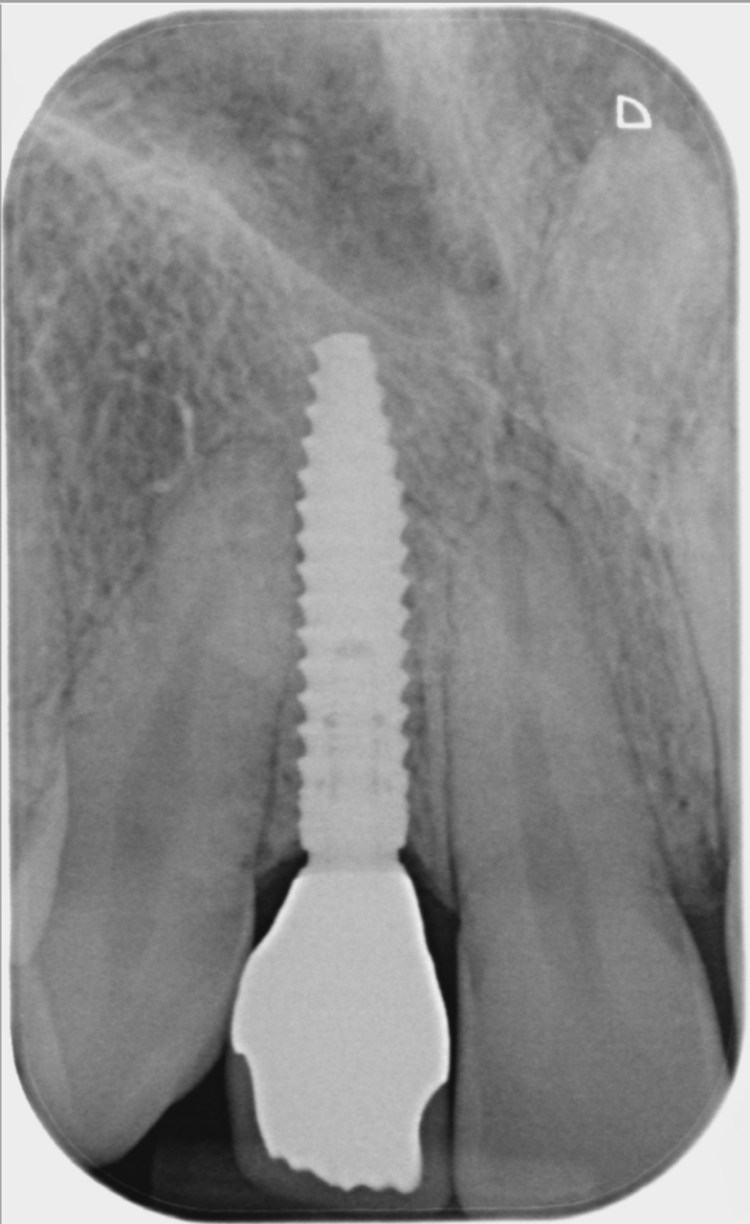

A week after the surgery, the patient was seen for a healing review, during which X-rays were taken and sutures were removed. After sufficient healing, the patient returned for an impression appointment, where the temporary teeth were removed and scans were taken to fabricate the final crowns.